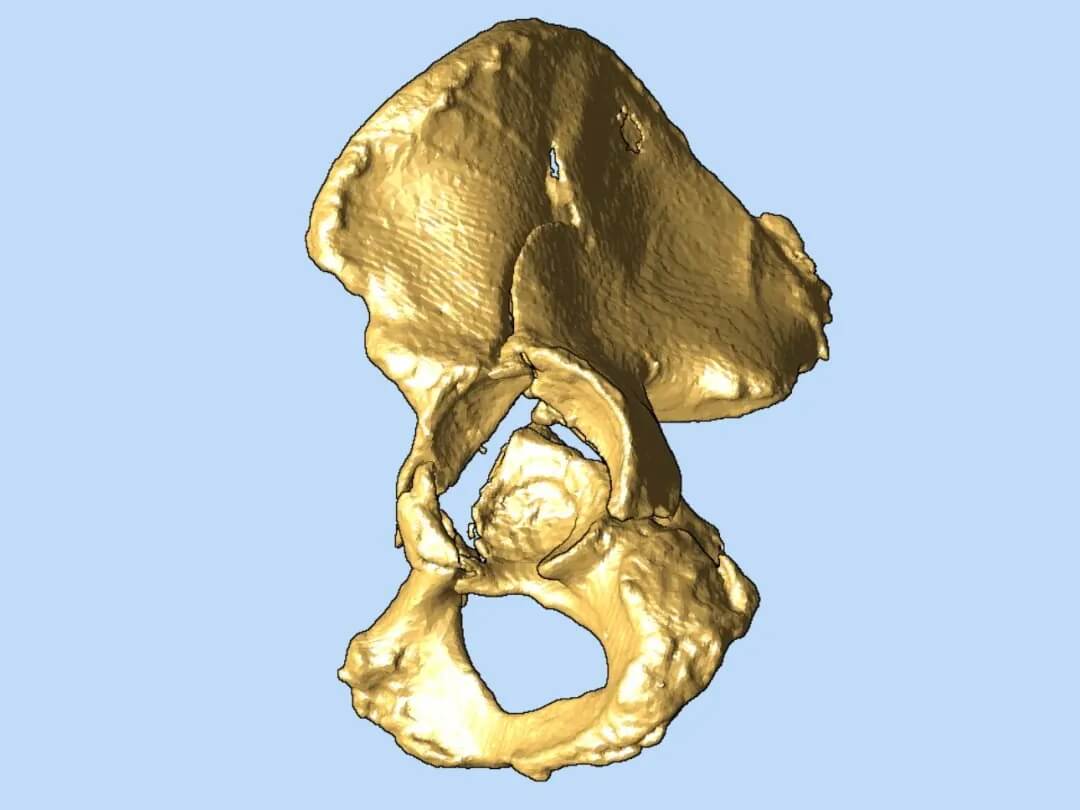

3D打印助力精準重塑骨盆

在腔靜脈濾器成功植入,患者安全度過血栓脫落風險的高危期后,羅軍團隊將利用先進的3D打印技術,為患者量身定制骨盆骨折修復方案?;诨颊逤T數(shù)據(jù)打印出的1:1精準骨盆模型,能讓醫(yī)生在術前清晰掌握粉碎骨塊的形態(tài)、位置,實現(xiàn)極致的手術可視化和方案個性化,顯著提高手術精準度、減少創(chuàng)傷、縮短手術時間,最終目的是促進患者獲得最佳的功能恢復。